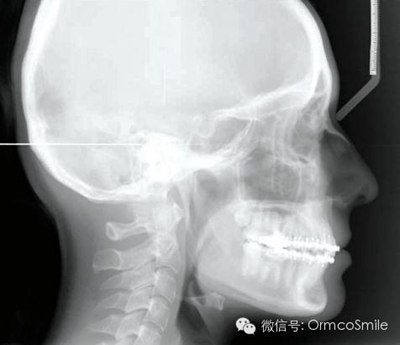

頭影測(cè)量分析顯示,SNA為80.9°,SNB為79.5°,ANB為1.4°,SN-GoMe角為25.5°,下切牙到NA的角度為22°、距離為4mm,上頜切牙與NA角度為18°、距離為4mm,上唇在E線后5mm,下唇在E線后3mm,鼻唇角為110°。

治療目標(biāo)為:遠(yuǎn)中移動(dòng)上頜右側(cè)磨牙,達(dá)到安氏Ⅰ類尖牙、磨牙關(guān)系。治療前,拔除上頜左側(cè)第三磨牙,將一直徑2mm,長(zhǎng)14mm的鈦骨釘植入上頜腭中縫,位于切牙孔后4-5mm,中線旁3-4mm。用1.3mm直徑的鉆助攻植入螺紋釘。一周之后,取印模并灌制模型,將螺紋釘?shù)念^部用蠟包圍,從螺紋釘上延伸出連接第一前磨牙的0.8mm的鋼絲??趦?nèi)試戴后,用光固化樹脂將從螺紋釘上延伸出的弓絲與上頜第一前磨牙粘接在一起,0.016*0.022英寸不銹鋼絲片段弓加鎳鈦推簧置于上頜第一磨牙和第一前磨牙間,每側(cè)250g力推動(dòng)上頜磨牙向遠(yuǎn)中,磨牙到位后拍攝頭側(cè)位片。

經(jīng)測(cè)量,上頜第一磨牙遠(yuǎn)中移動(dòng)3.5mm,達(dá)到磨牙Ⅰ類關(guān)系,同時(shí)壓低2mm,而第一前磨牙和上頜切牙沒有明顯的移動(dòng)。上頜第一前磨牙有3°的輕度前傾,這可能是由于上頜只植入了1顆螺紋釘?shù)脑?,作者分析采用兩顆螺紋釘可以減少這種副作用。在上頜磨牙遠(yuǎn)中移動(dòng)過程中,下頜平面角減少了1°,且其持續(xù)到正畸治療結(jié)束。上頜牙弓寬度有輕度擴(kuò)大。